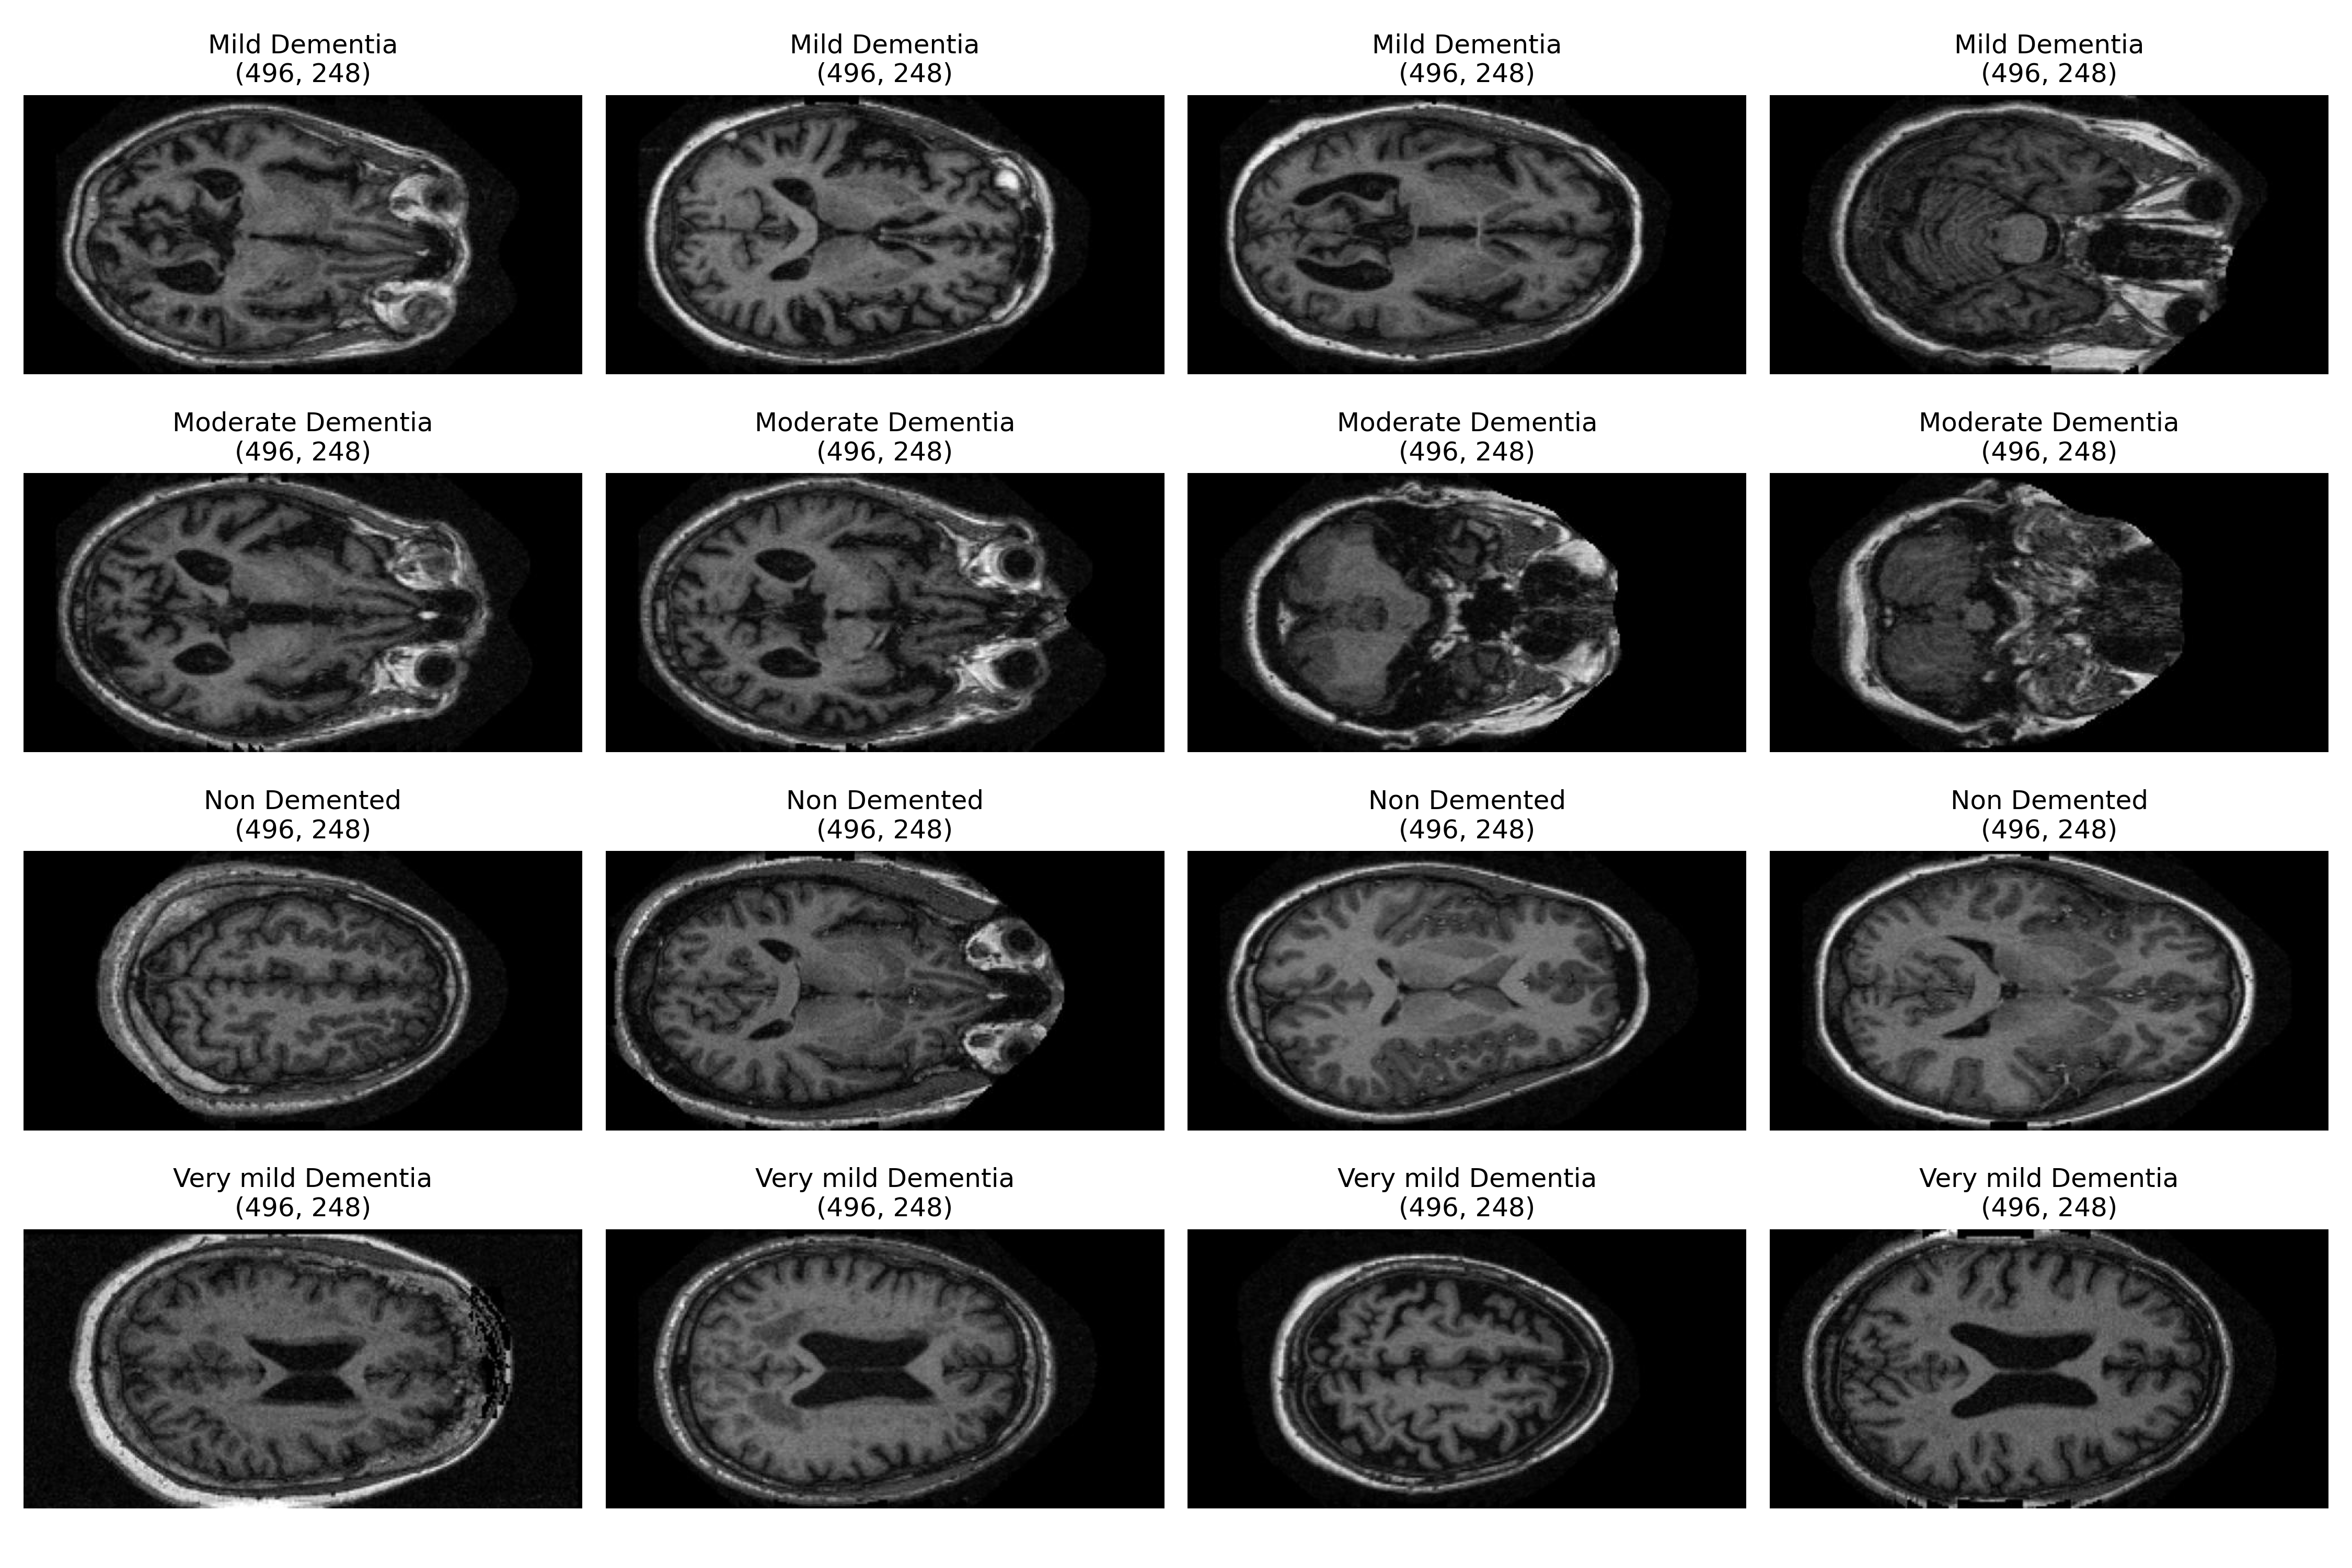

The Alzheimer data collected from Kaggle [23]. The actual data is from Open Access Series of Imaging Studies (OASIS) MRI dataset[27]. The dataset contains over 80 thousand brain MRI images. The images have been divided into four classes based on Alzheimer’s progression and these are Mild Dementia, Moderate Dementia, Non Demented, Very mild Dementia. The original MRI scans were converted from .img/.hdr to Nifti (.nii) format using FSL. For training, 2D brain slices (slices 100–160 along the z-axis) were extracted, creating a rich dataset. Patients were classified into four categories—non-demented, very mild, mild, and demented—based on Clinical Dementia Rating (CDR) values. Here, Mild Dementia has 5002 images, Moderate Dementia has 488 images, Non Demented has 67,222 images, and Very mild Dementia has 13,725 images. Fig 2 shows the image sample of the Alzheimer MRI scans.

Refer to caption

Figure 2: Data Sample